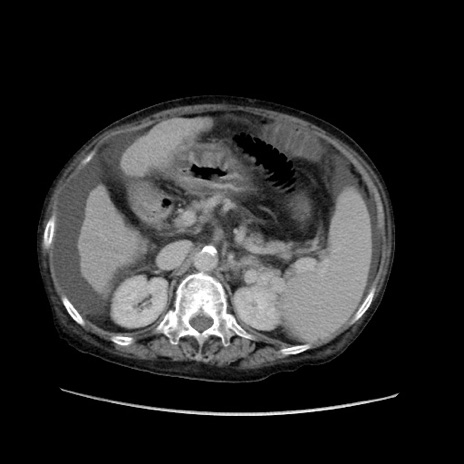

症例31(横断像)

【症例】80歳代 女性

【主訴】腹部膨満感

【現病歴】他院にて肝硬変にてフォロー中。1週間前から便秘、腹部膨満感、臍部腫瘤あり受診となる。

【既往歴】肝硬変

【身体所見】腹部膨隆あり、皮膚変化なし、疼痛なし。

【データ】WBC 4600、CRP 0.25